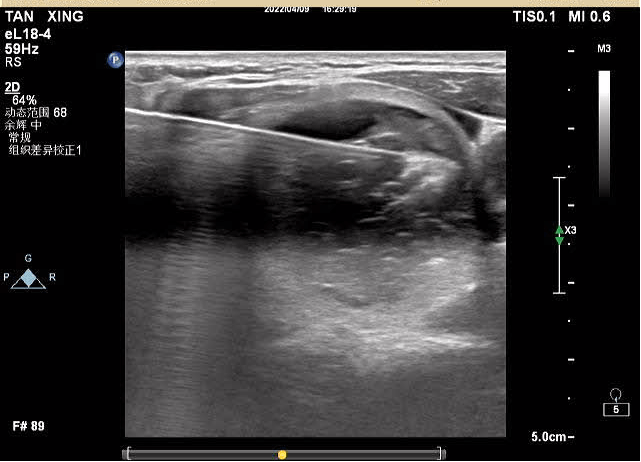

對(duì)結(jié)節(jié)實(shí)性部分進(jìn)行移動(dòng)式+固定式射頻消融